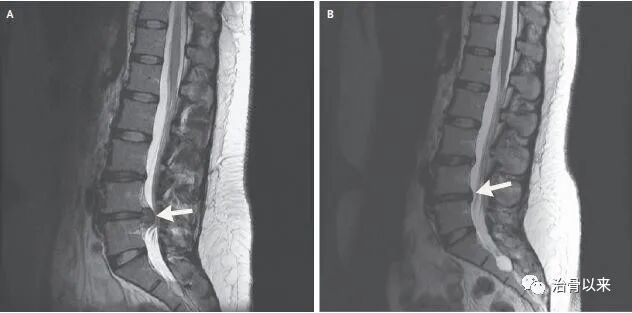

我们以前讲过,曾有一位29岁的女性被确诊为腰椎间盘突出,如下图A。经过5个月的杨顾生中药酒保守治疗之后,她的MRI影像显示腰椎间盘突出已回纳,如下图B。